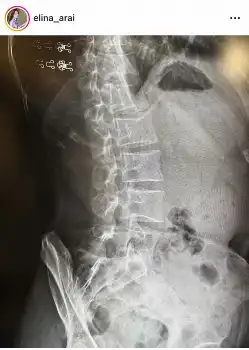

新井は「レントゲン写真って、レイヤーがいくつもある感じでなんだか綺麗~…というのは個人の感想でしょうか?笑」と腰回りのレントゲン写真を投稿した。

レントゲンを撮影した理由については「ヘルニアではありませんでしたがはじめて、所謂ぎっくり腰になりました」と明かした。

そして「翌日は、薬局でコルセットを買ってきてもらってつけて、なるべく安静に。次の日に病院でレントゲンを撮ってもらい、理学療法を施してもらい、薬による痛み止めで治るのを待つことになりました」と状況を説明した。